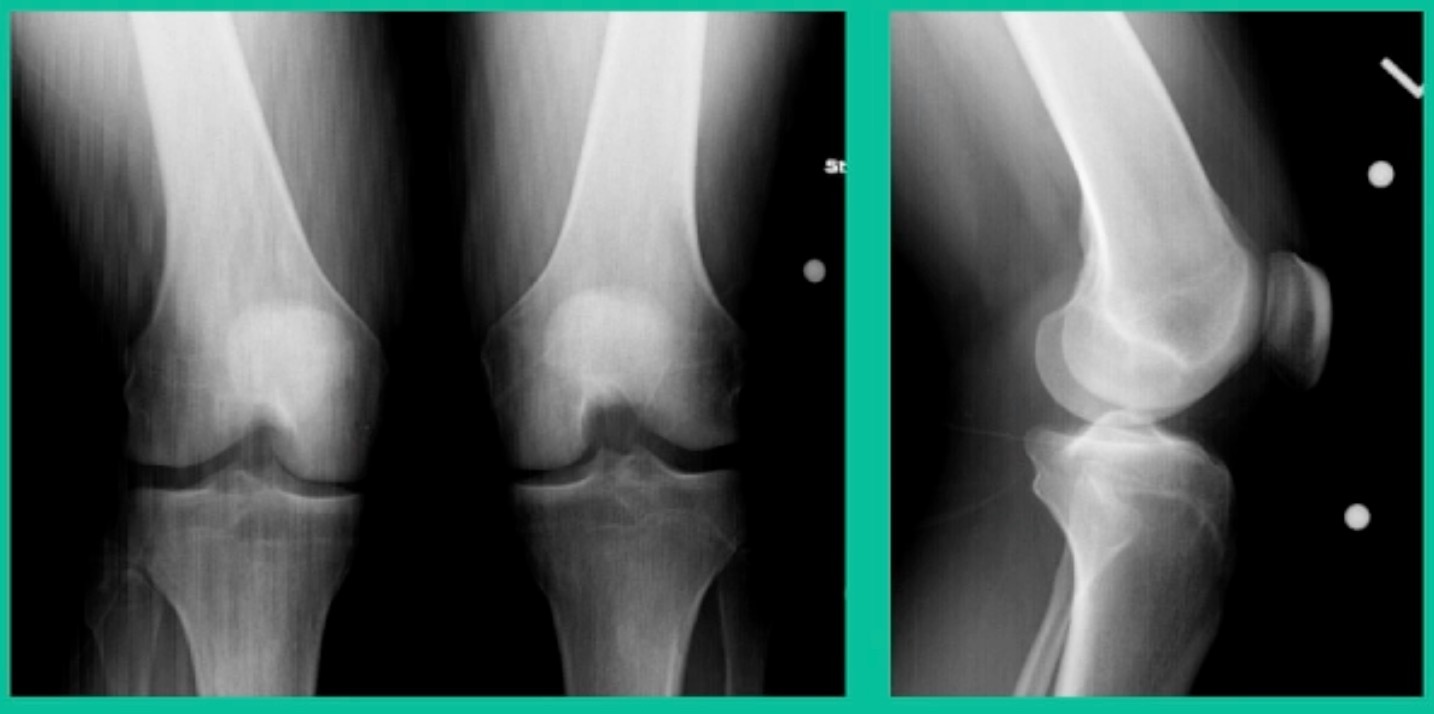

Another one. 24-year-old right knee pain, ADL discomfort, normal alignment, lots of symptoms, thought I might be able to fix it.

I get in there, the pieces are just fragmented, I’m not going to fix it. This is the lateral aspect medial femoral condyle. Statistically, this one can do well. You take the piece out, they say, “I feel better.” It’s on the upslope of the lateral aspect medial femoral condyle. They feel fine, right? That’s not the case here. This one still continued to have symptoms.

So, what do we do for this one? This one got an osteochondral allograft.

I gave you a whole talk earlier on today about OA grafts. This is my mainstay for a salvage. I do not pull this out of the bag when the patient walks in the office for their first-line treatment. First, they get a scope. If it can’t be fixed, it comes out. If it can be fixed, we fix it with metal screws if it’s grossly unstable. If it’s not grossly unstable, we use biocomposite screws. If they get fixed, they go back to sports in four months. If they fail, they generally get this (Figure 28).